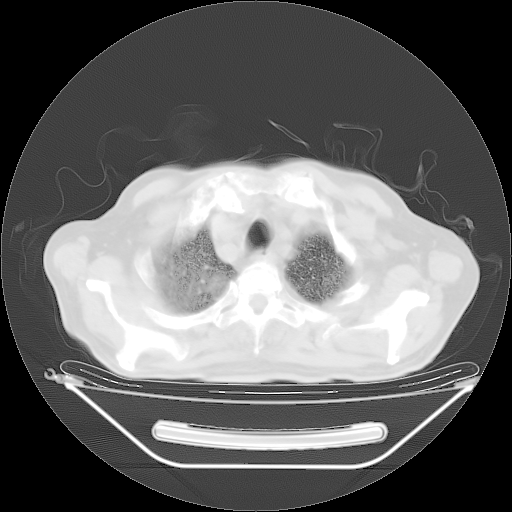

胸腹部CT,诊断意见:左上肺叶钙化灶、左侧胸膜局限性增厚并钙化、胆囊炎。描述部分肺组织呈磨玻璃样改变。